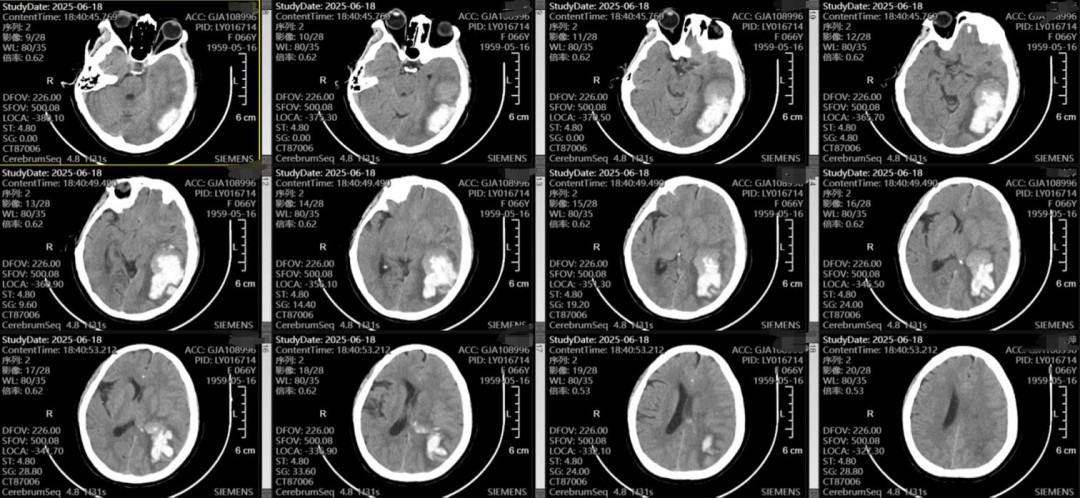

随着老龄化的加剧,脑出血的患者越来越多,不同部位的脑出血,可能因不同的原因导致,该患者左侧颞枕叶脑出血,吴全主任考虑脑血管畸形可能较高,但患者意识渐昏迷,先行血肿清除,但骨窗主要位于后枕顶部,若是去除骨瓣,不利于术后脑组织的保护,且后期需要颅骨修补,故与患者家属充分沟通后,予以骨瓣回纳,术后治疗上加强脱水,帮助患者渡过脑水肿关,患者术后第一天意识即转清楚。后期待病情平稳后在行DSA检查评估,明确此次出血是否为脑血管畸形、动脉瘤等原因导致的出血。